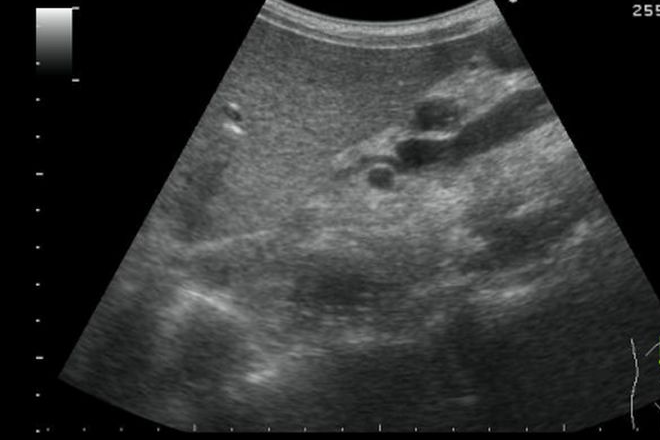

Desde el punto de vista ecográfico, la pancreatitis aguda se caracteriza por un a umento difuso y generalizado del tamaño del páncreas, junto a unos límites o contornos algo imprecisos y disminución de la ecogenicidad, en ocasiones incluso con refuerzo acústico posterior. En casos de pancreatitis aguda grave, se observan heterogeneidad parenquimatosa, con lesiones focales hipo o anecogénicas, desestructuración glandular, líquido libre y alteración de la visualización de los vasos vecinos. Sin embargo, se puede obtener una ecografía normal en pacientes con pancreatitis aguda moderada, del mismo modo que según algunas series, el 14% de los pacientes no muestran alteraciones significativas en el TAC.

– Dilatación irregular del conducto de Wirsung (lo que llamamos un Wirsung arrosariado): un conducto de Wirsung de más de 3 mm se considera dilatado, siendo este un hallazgo frecuente en la pancreatitis crónica, aunque también se puede visualizar en otras entidades como el cáncer de páncreas.

– Litiasis ductal o parenquimatosa: en ocasiones, en el Wirsung dilatado se pueden encontrar litiasis.